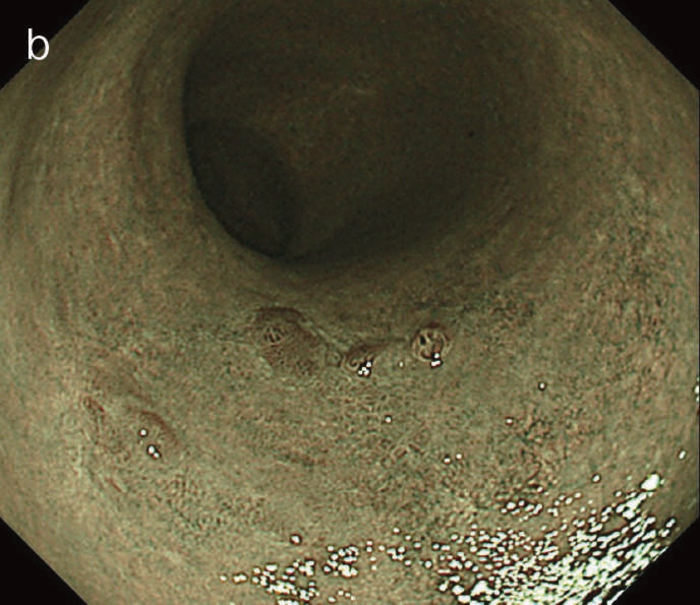

図6 UC関連LGDの内視鏡所見

- 白色光像:直腸(下部直腸)に色調変化は乏しく,微小な隆起を複数認めた。背景粘膜は寛解期にあった。

- NBI非拡大像:Brownishな領域が明らかとなった。

- 色素内視鏡像:病変辺縁が明瞭な微小な隆起を複数伴う表面平坦型病変。

- NBI拡大像:口径整でらせん状の微小血管と絨毛状の表面構造を認めた。

- pit pattern像:小型の類円形,管状pitを認めた。